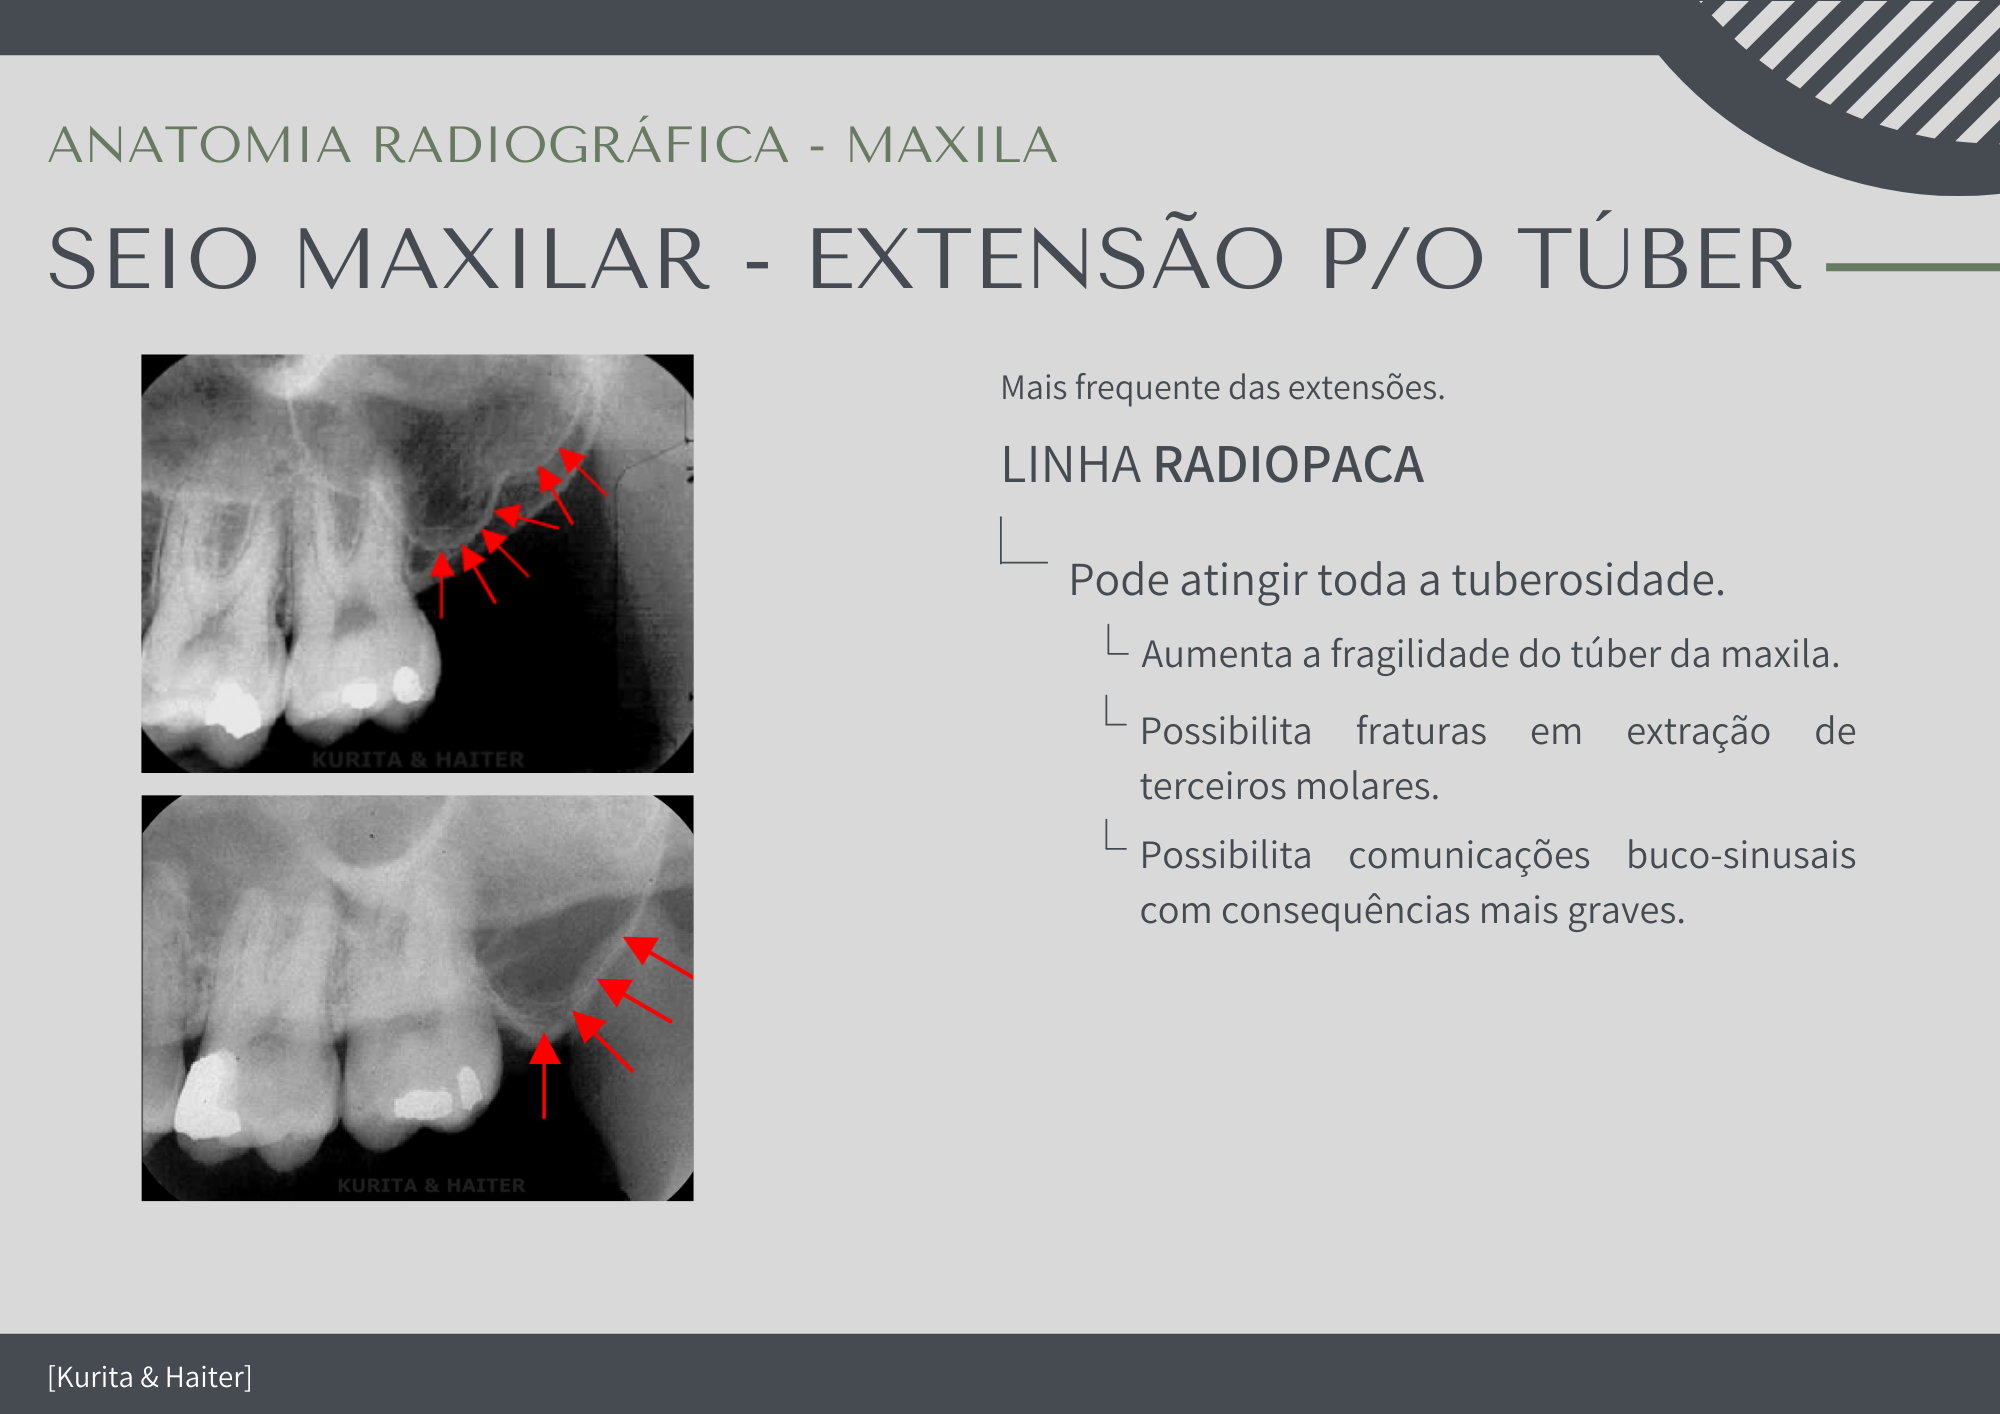

Extensão Alveolar Do Seio Maxilar

Raios X Seios Da Face – Método De Caldwell - Concursos Já Brasil

Radiologia: Raio-X Seios Da Face

seios raio seio faciais sinusite nomes os raios cavidades nasais radiologia radiografia alternativos são